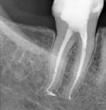

In the past years the heat-treated Ni-Ti rotary files have become a gold standard in endodontics. However, heat-treated nickel-titanium endodontic instruments produced with the electro discharged machining are on a completely another level offering some unparalleled properties. Scientific studies show surprisingly high values of cyclic fatigue resistance, increased cutting efficiency and increased wear resistance with low degradation. The HyFlex EDM files systems offer the user a simple, predictable, safe, and cost-effective instrumentation in all clinical types of root canals, form straight to severely curved. The new OGSF sequence makes it possible to enlarge the root canal in a minimally invasive way to 30/0.04, making the EDM system even more versatile. If needed the root canals can be enlarged with EDM Hyflex 40/0.04, and further with the reducing taper from 50/0.03 to the file size up to 60/0.02 without loosing on the flexibility of the files to best preserve the original shape of the root canal all the way to the apex. Pre-bending the controlled memory EDM files also offers a simple management for by-passing ledges previously formed in the root canal. The HyFlex EDM system is the system of choice for beginners and advanced users.